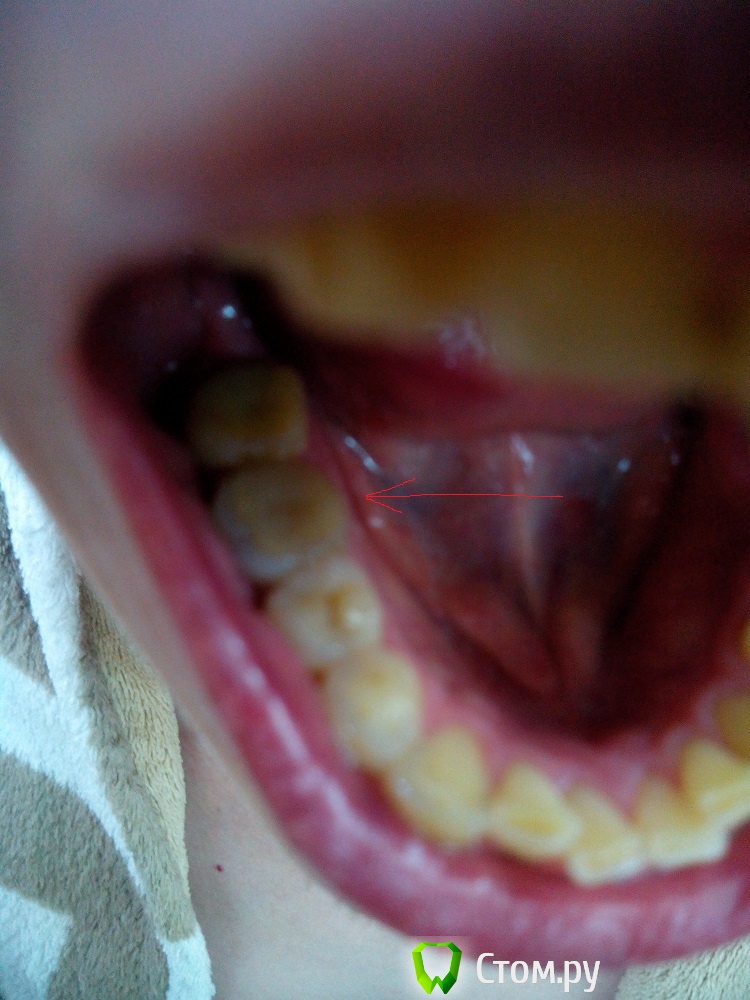

IvanK Опубликовано 16 июня, 2014 Поделиться Опубликовано 16 июня, 2014 Если судить только по снимку - зуб нужно удалять, ввиду сильного разрушения, ниже уровня десны+1 фото бы посмотреть Ссылка на комментарий

edw Опубликовано 16 июня, 2014 Автор Поделиться Опубликовано 16 июня, 2014 пока сфоткал так, как смог Ссылка на комментарий